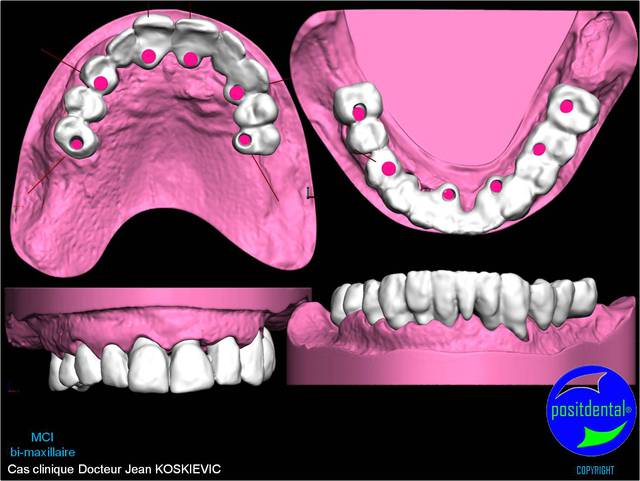

06/05/2011 à 16h22

Montage esthétique ou wax-up 3D

S.I.A.O.